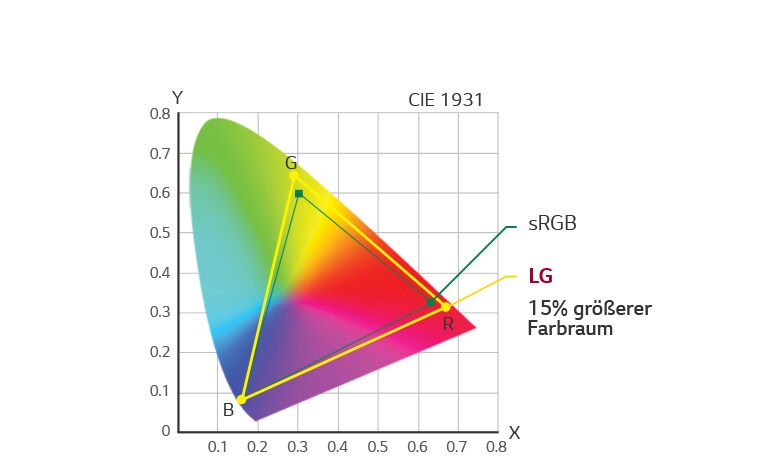

115% sRGB (Bereich), über 99% sRGB (Abdeckung)

Der OP-Monitor 32HL714S unterstützt 115% sRGB (Farbraum) und über 99% sRGB (Farbabdeckung) sowie den Standard DICOM Part 14 und wurde für eine genaue Farberkennung und Tiefenwahrnehmung während chirurgischer Eingriffe entwickelt. So können Chirurgen genaue, realitätsgetreue Bilder betrachten und Operationen präzise durchführen.